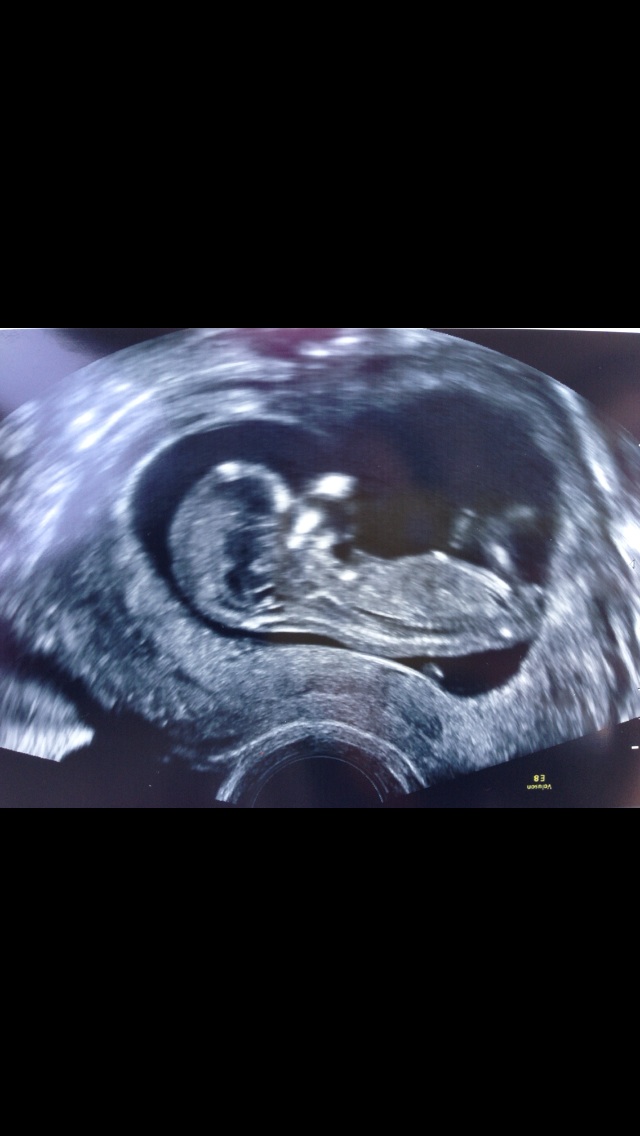

Here is a picture of my ultrasound. Any guesses on the gender would be much appreciated!